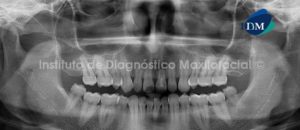

Paciente de sexo femenino y de 59 años de edad es referida al Instituto de Diagnóstico Maxilofacial para realizar el estudio de evaluación ósea para la colocación de implantes, lo cual llamo nuestra atención la presencia de un hallazgo radiográfico en el maxilar inferior.